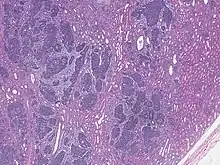

High magnification micrograph showing the three elements of Wilms' tumor. H&E stain.

Pathologically, a triphasic nephroblastoma comprises three elements:[11]

Wilms' tumor is a malignant tumor containing metanephric blastema, stromal and epithelial derivatives. Characteristic is the presence of abortive tubules and glomeruli surrounded by a spindled cell stroma. The stroma may include striated muscle, cartilage, bone, fat tissue, and fibrous tissue. Dysfunction is caused when the tumor compresses the normal kidney parenchyma.